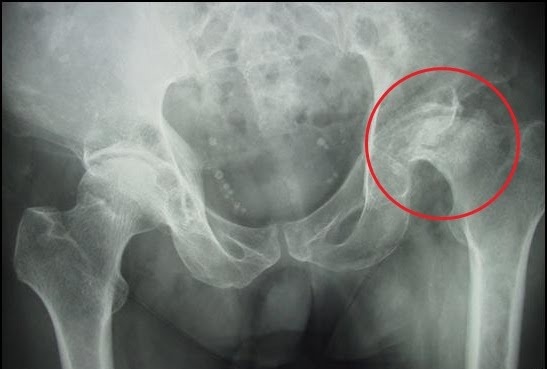

| Bệnh nhân hoại tử chỏm xương đùi. Ảnh: Sites.google |

Bác sĩ Khánh cho biết đây là tình trạng chỏm xương đùi (một bộ phận cấu thành của khớp háng) bị hoại tử do thiếu máu nuôi. Khi chúng ta bắt đầu thấy đau khớp háng có nghĩa bệnh đã âm thầm tiến triển một thời gian. Giải pháp hữu hiệu và triệt để nhất để điều trị căn bệnh này là phẫu thuật thay khớp háng. Các giải pháp như uống thuốc, tập phục hồi chức năng, khoan giảm áp -tế bào gốc,…đều chỉ mang tính tạm thời với mục đích kéo dài thêm thời gian trì hoãn mổ.

Căn bệnh này gặp chủ yếu ở nam giới (khoảng 80%). Trước đây, độ tuổi trung bình bị bệnh dao động 40-50, nhưng hiện có xu hướng trẻ hóa rất rõ ràng, nhiều nam thanh niên chỉ 30 tuổi đã bắt đầu hoại tử chỏm xương đùi.

Để chẩn đoán chính xác bệnh này, bệnh nhân cần chụp X-quang khung chậu, kết hợp với chụp cộng hưởng từ khớp háng. Cộng hưởng từ là một bước tiến vượt bậc trong chẩn đoán bệnh, trong đó có bệnh lý các khớp.